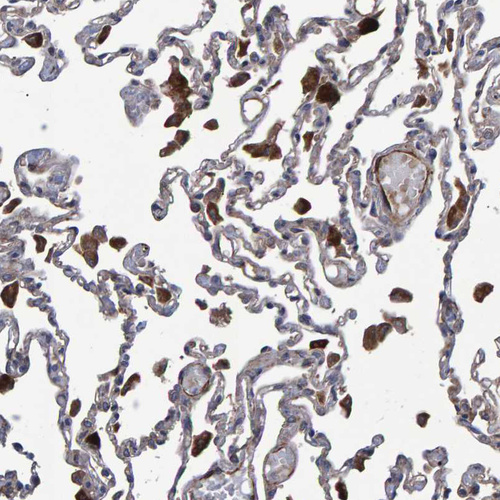

Immunohistochemical staining of human lung shows strong cytoplasmic positivity in macrophages.